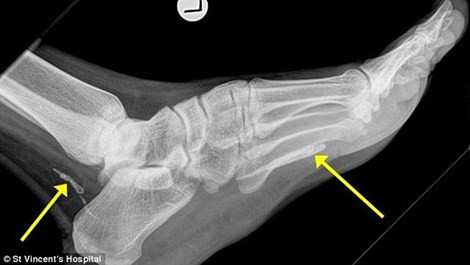

Ảnh chụp X quang cho thấy những phần còn lại của con giun

Người đàn ông này đã đến Úc vào 4 năm trước, gần đây anh ta tới gặp bác sỹ để khám bàn chân do nó sưng phù mãi không hết suốt 1 năm. Tiến sỹ, bác sỹ chuyên về bệnh truyền nhiễm Jonathan Darby đã thấy trong phim X quang 2 mảnh của con “giun Guinea” cuộn tròn trong phần mắt cá và bàn chân người đàn ông. Sinh vật này có thể đã chết vì ... già và bắt đầu phân hủy trong cơ thể anh ta.